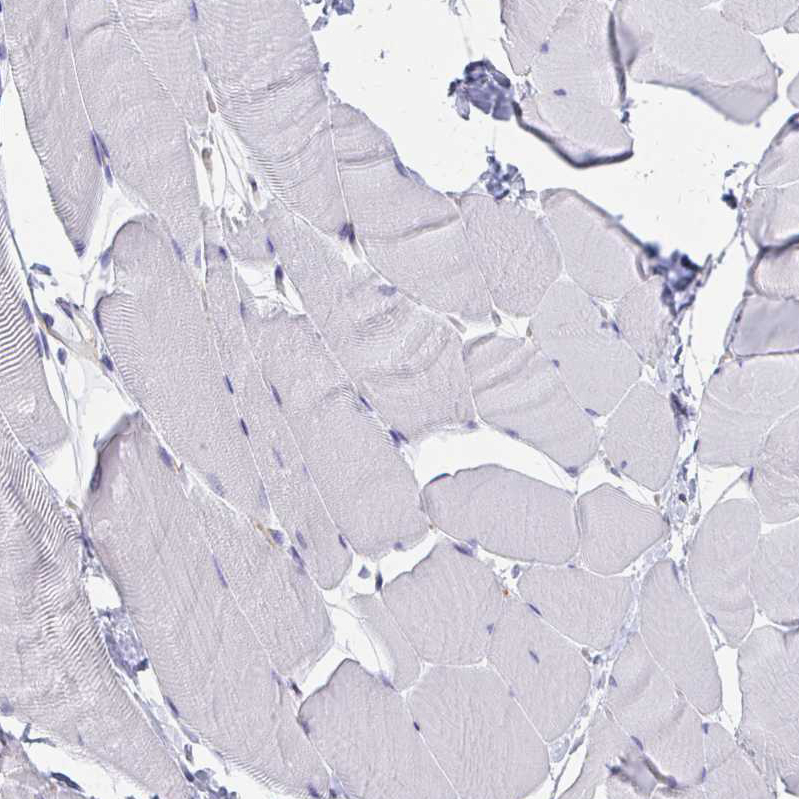

Immunohistochemistry analysis in human testis and skeletal muscle tissues using HPA030528 antibody. Corresponding MARCKSL1 RNA-seq data are presented for the same tissues.